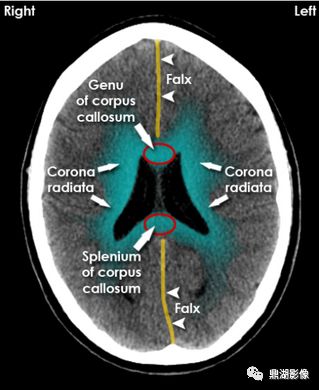

Falx:大脑镰;Genu corpus callosum:胼胝体膝部;Splenium corpus callosum:胼胝体压部;corona radiata:放射冠